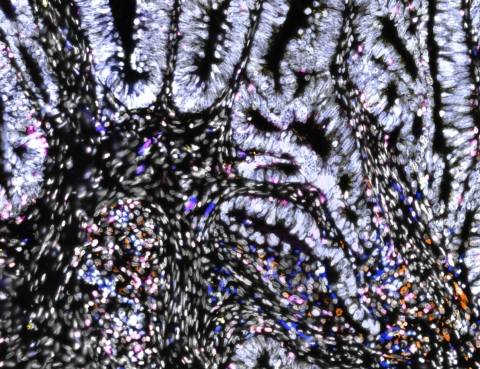

LAUSANNE, Switzerland– Lunaphore, a Swiss life sciences company developing technology to enable spatial biology in every laboratory, today announced it will host a virtual scientific talk in partnership with Labroots on October 21, 2021, about spatial “omics” methods as a laboratory service. Dr. Charlotte Stadler, Head of the National Spatial Proteomics Facility and platform coordination officer for the Spatial and Single Cell Biology Platform at SciLifeLab, a world-renowned institute in Sweden focused on the advancement of molecular biosciences, will discuss the incorporation of spatial proteomics technologies in service laboratory workflows. The talk will focus on how her facility is utilizing COMET™, Lunaphore’s all-in-one staining and imaging platform for high-throughput, hyperplex immunofluorescence, to explore the cellular landscape across several tissue types.

In the webinar, Dr. Stadler will discuss multiplexed spatial proteomics using sequential immunofluorescence and show results obtained with COMET™. The Spatial and Single Cell Biology (SSCB) platform at SciLifeLab expects to fully integrate COMET™ into its workflow and offer it as a service next year.

“The COMET™ system allows for systematic development of multiplexed panels for a variety of tissues,” said Dr. Stadler. “Using sequential indirect immunofluorescence, one’s existing set of validated primary antibodies can be optimized and used in a multiplexed manner.”